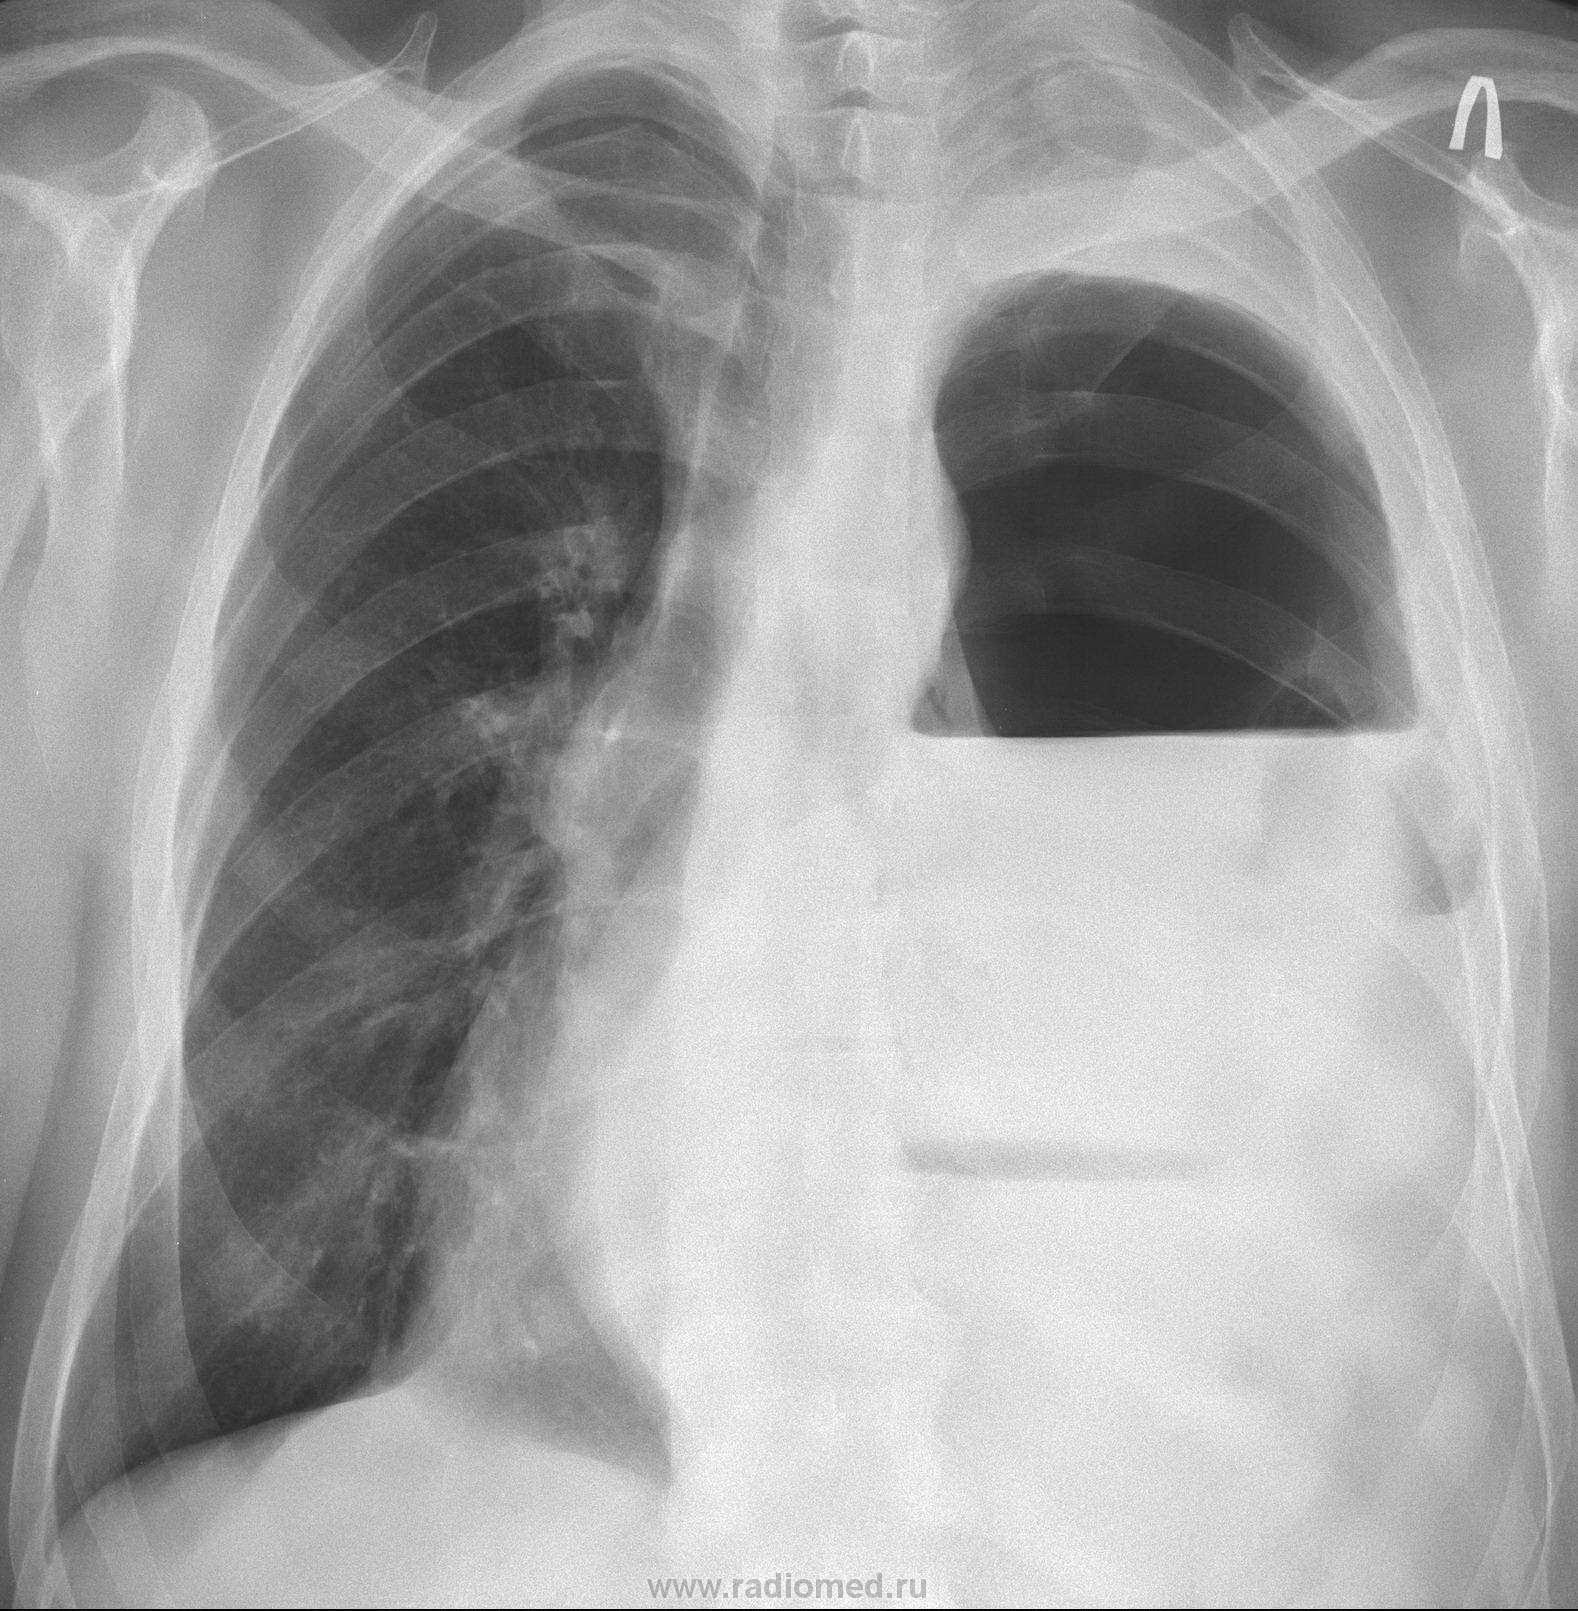

Извеняюсь с задержкой, проблема с интернетом, данный пациент поступал ещё пол года назад, с предворительным диагнозом: Диафрагмальная грыжа слева? Тотальный гидропневмоторакс слева? Мы просто дали ему рентген-контрастное под контролем скопии.

Очень интересная картинка, но такую картинку может обусловить, отнюдь, не одна патология. А посему, надо "колоться", уважаемый коллега", и выкладывать продолжение...

Смею предположить реласацию левого купола диафрагмы и заворот желудка. По крайней мере были подобный случаи (дважды).

Я задал этот вопрос, так как считаю, что пол года тому была травма, и не хилая, были и переломы ребер слева, которые видны на снимках, и как следствие пневмоторакс, трансформировавшийся позднее в гидропневмоторакс, я даже допускаю, что был травматический радрыв (разрыв) диафрагмы, что послужило воротами для пролабирования желудка в грудную полость.